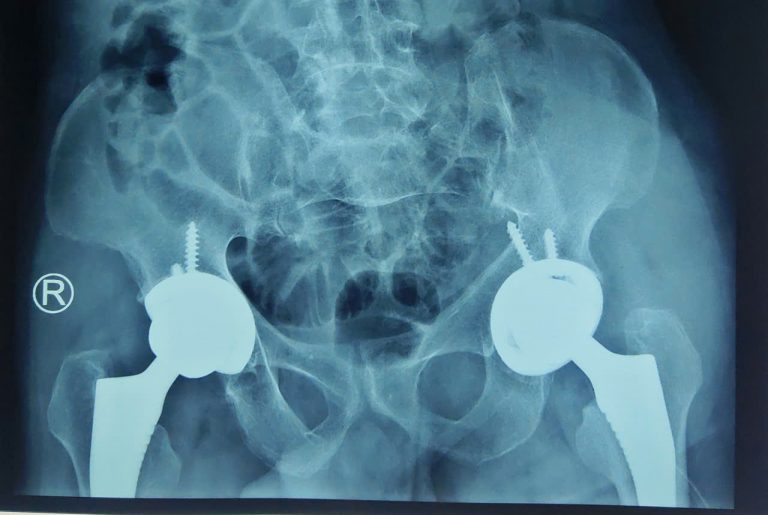

Ghép tạng là 1 trong 10 thành tựu y học lớn nhất của nhân loại trong thế kỷ 20. Đây là giải pháp duy nhất mang lại hy vọng sống cuối cùng của người bệnh khi các phương pháp khác không còn hiệu quả. Tại Việt Nam, ban đầu ghép tạng chỉ là ước mơ, đến nay, chúng ta bắt đầu làm chủ những kỹ thuật hiện đại nhất. Phép màu tái sinh cuộc đời nữ bác sĩ trẻ Chị Nguyễn Thị Phương Nhi, 32 tuổi, là bác sĩ sản khoa, công tác tại Bệnh viện Đa khoa Phương Bắc, Tuyên Quang. Chị từng không nghĩ rằng, “hành trình cứu người” của mình lại có ngày phải tạm dừng trước một bước ngoặt sinh tử. Sáu năm trước, chị được chẩn đoán mắc bệnh cơ tim giãn – căn bệnh âm thầm bào mòn chức năng tim, đẩy người bệnh đến ranh giới mong manh giữa sự sống và cái chết. Thời gian phát hiện mắc bệnh đúng trong lần chị mang thai đầu tiên. Sau khi sinh con, chị kiên trì điều trị nội khoa, bền bỉ chống chọi với những tháng ngày mệt mỏi kéo dài. Bất ngờ, một cơn suy tim cấp ập đến, tình trạng bệnh trở nên nguy kịch, buộc chị phải chuyển tuyến điều trị. Tại đây, các bác sĩ xác định con đường duy nhất để giữ lại sự sống cho chị là ghép tim. Chồng chị cũng là một bác sĩ chẩn đoán hình ảnh. Hai vợ chồng cùng học tại Đại học Y Thái Bình, sau đó công tác tại Tuyên Quang. Anh là người dân tộc Khơ Mú, ở Điện Biên, còn chị ở Thanh Hóa. Đôi vợ chồng trẻ có một cô con gái – là nguồn động lực lớn nhất giúp chị Nhi bám víu vào sự sống trong những ngày dài trên giường bệnh. Giữa lằn ranh sinh tử, phép màu đã tìm đến chị. Sau 5 năm chống chọi với bệnh cơ tim giãn, chị được hồi sinh nhờ một ca ghép tim từ người hiến chết não. Tháng 1/2025, chị được ghép tim thành công tại Bệnh viện Hữu nghị Việt Đức. Ba tháng sau ghép, chị đã quay lại công việc hàng ngày, đó là thăm khám và điều trị ngoại trú cho nhiều người bệnh. Đến nay, chị cảm nhận rõ sức khỏe thay đổi từng ngày, khỏe khoắn hơn, tinh thần lạc quan hơn rất nhiều, nhất là khi được quay trở lại công việc phục vụ người dân. Khoác lại chiếc áo blouse trắng với trái tim được hồi sinh, chị Nhi xem đó như một lời tri ân lặng thầm và sâu sắc tới gia đình người hiến tạng, đã trao cho chị không chỉ một trái tim, mà cả một cuộc đời mới. Chị Nhi là 1 trong nhiều người bệnh ở nước ta được hồi sinh từ lằn ranh sinh tử trong những năm trở lại đây, nhờ kỹ thuật ghép tạng đỉnh cao của nhân loại. Ghép tạng là một trong 10 thành tựu y học lớn nhất của nhân loại trong thế kỷ 20. Đây là giải pháp duy nhất mang lại hy vọng sống cuối cùng của người bệnh khi các phương pháp khác không còn hiệu quả. BS Nguyễn Thị Phương Nhi đang công tác tại Tuyên Quang. Từ ước mơ đến tầm nhìn chiến lược… Trên thế giới bắt đầu nghiên cứu ghép tạng từ đầu thế kỷ XX, đến năm 1954 bắt đầu ghép thận thành công; năm 1963 ca ghép gan đầu tiên được tiến hành và đến năm 1967, ca ghép gan đầu tiên thành công. Tại Việt Nam, từ những năm 60 thế kỷ XX, y học Việt Nam còn thiếu thốn về trang thiết bị, cơ sở vật chất, thuốc men và nhân lực. Ghép tạng khi đó chỉ là ước mơ đối với giới y học trong nước và bệnh nhân bị suy tạng cần điều trị thay thế. Tuy nhiên, với tầm nhìn chiến lược về ghép tạng tại Việt Nam từ những năm 1970, Giáo sư, Viện sĩ Tôn Thất Tùng, Cố Giám đốc Bệnh viện Hữu nghị Việt Đức đã không ngừng nỗ lực nghiên cứu ghép tạng và đã ghép thành công ở động vật từ năm 1965-1966. Mong muốn của GS Tôn Thất Tùng là thực hiện ghép gan, thận cho người vào những năm 1970. Song, thời gian đó, cả nước phải tập trung nhân lực, vật lực cho kháng chiến nên ý nguyện của Giáo sư không thực hiện được. Mặc dù vậy, với sự kiên định, bản lĩnh, tầm nhìn lớn, GS Tôn Thất Tùng đã gửi các chuyên gia đi học ở nước ngoài với nhiều chuyên ngành khác nhau như nội, ngoại, gây mê hồi sức, chẩn đoán hình ảnh… nhằm chuẩn bị sẵn lực lượng cho ngành ghép tạng nước nhà. AHLĐ.TTND.GS Nguyễn Tiến Quyết, Phó Chủ tịch Hội Ghép tạng Việt Nam – Ảnh: VGP Và những dấu ấn kỳ tích trong đời thực Theo Anh hùng lao động, Thầy thuốc nhân dân, GS Nguyễn Tiến Quyết, Phó Chủ tịch Hội Ghép tạng Việt Nam, chuyên gia đầu ngành về ghép tạng và hơn 40 năm kinh nghiệm về chuyên khoa ngoại tiêu hóa – gan mật tụy, đến năm 2000, khi có đủ cơ sở vật chất, nhân lực, vật lực, chúng ta đã tiến hành ghép tạng trên động vật rất hiệu quả. Bệnh viện Hữu nghị Việt Đức đã triển khai thành công nghiên cứu ghép gan thực nghiệm trên động vật (lợn). Hoạt động này nằm trong đề tài nghiên cứu cấp nhà nước: “Nghiên cứu một số vấn đề ghép gan để thực hiện ghép gan trên người tại Việt Nam”. Sự kiện đã mở ra một cơ hội lớn cho kỹ thuật ghép gan của Bệnh viện Hữu nghị Việt Đức nói riêng và cả nước nói chung. Đó cũng là kết quả ngọt ngào sau những chuỗi